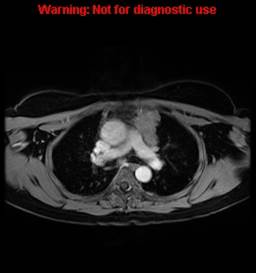

Please review the result by clicking on each image.

What is the most likely cause of the anterior mediastinal mass shown in these images? (You may select more than one option.)